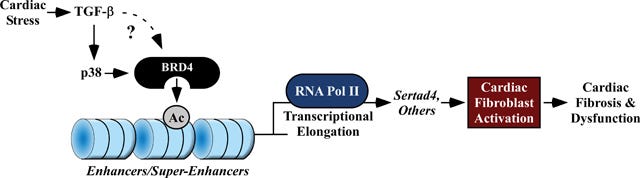

Stratton et al (2019) conducted an in vitro study to support the hypothesis that BRD4 controls activation of fibroblasts20:

Objective: We sought to test the hypothesis that BRD4 functions in a cell-autonomous and signal-responsive manner to control activation of cardiac fibroblasts, which are the major extracellular matrix (ECM)-producing cells of the heart.

Method and Results: RNA-sequencing (RNA-seq), mass spectrometry and cell-based assays employing primary adult rat ventricular fibroblasts (ARVFs) demonstrated that BRD4 functions as an effector of TGF-β signaling to stimulate conversion of quiescent cardiac fibroblasts into Periostin (Postn)-positive cells that express high levels of ECM.

Conclusions: These findings define BRD4 as a central regulator of the pro-fibrotic cardiac fibroblast phenotype, establish a p38-dependent signaling circuit for epigenetic reprogramming in HF, and uncover a novel role for Sertad4. The work provides a mechanistic foundation for the development of BRD4 inhibitors as targeted anti-fibrotic therapies for the heart.